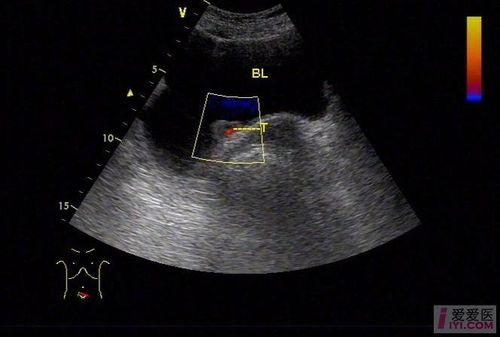

ct48821:膀胱占位